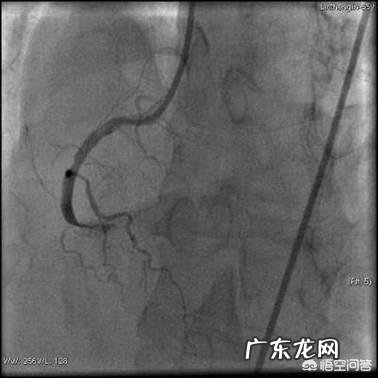

(右冠堵塞)